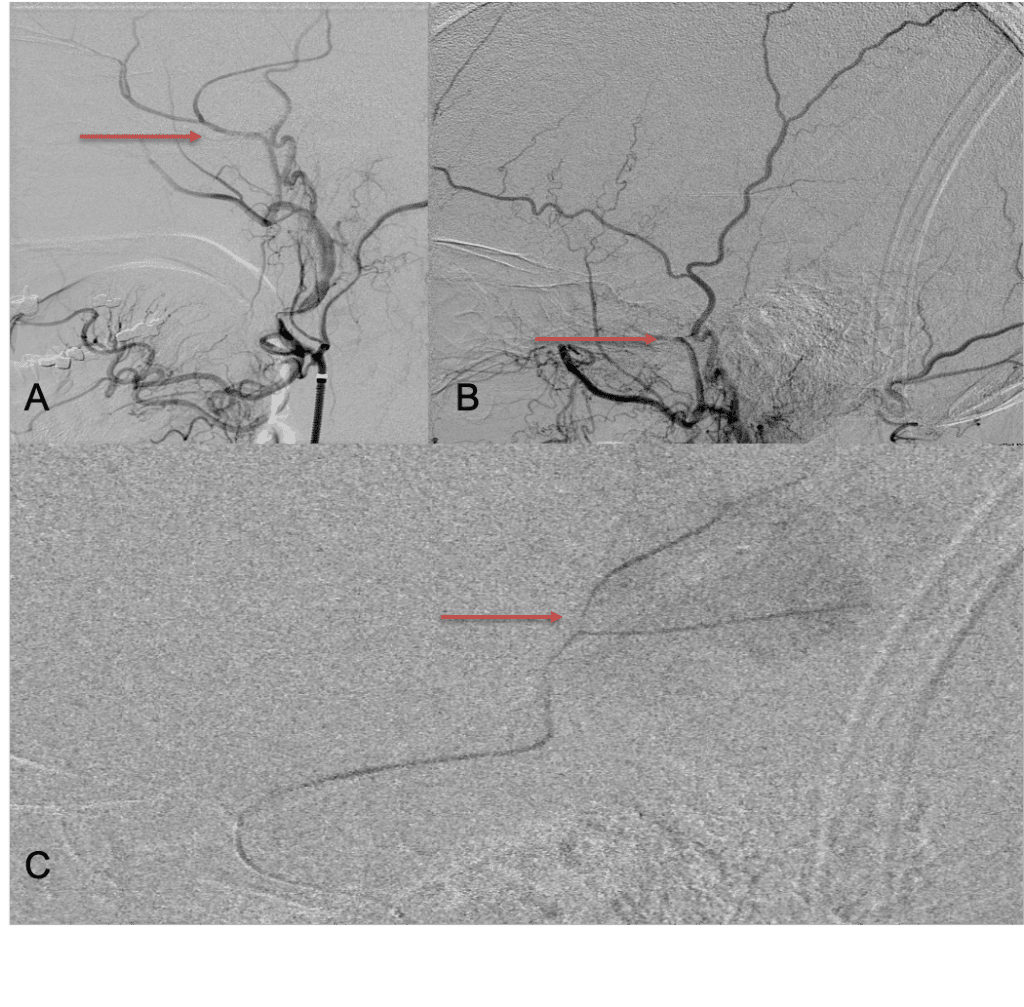

The patient agreed to receive minimally invasive treatment with Bilateral Middle Meningeal Artery Embolization, a new approach to promote resorption of chronic and subacute subdural hematomas in patients that are not improving with conservative measures or have contra-indications to surgical evacuation. Selective catheterization of the Middle Meningeal Artery is followed by transarterial embolization of the territory and inflammatory membranes that are felt to be secreting serosanguinous proteinaceous exceeding the capacity for resorption. MMA embolization was performed bilaterally in this patient. (Figure 2. A and B)

Figure 2. A) Initial right ECA angiogram ; B) Post MMA Embolization; C) Selective Embolization Of Middle Meningeal Artery Membranes using PVA particles (arrows).

Although conventional surgical methods, such as burr hole irrigation or observation in asymptomatic or minimally symptomatic patients have been the mainstay of treatment, middle meningeal artery (MMA) embolization has emerged as a promising adjunctive or alternative treatment. MMA embolization is a neuroendovascular technique which involves placing a microcatheter into the Middle Meningeal Artery, most commonly on the side of the cSDH (occasionally, bilateral embolization has been recommended for larger or bilateral collection. Embolization of both the anterior (frontal) and posterior (parietal) division is performed using a variety of embolic materials (liquid NBCA, Onyx, coils), although polyvinyl alcohol particles of <250 microns are most commonly used to achieve distal penetration and occlusion of the pre-capillary and capillary beds. The micro-leakage of blood and transudative proteinaceous inflammatory fluid in these inflammatory membranes is creating an imbalance in cycle of resorption and preventing resolution or promoting recurrence or growth of these cSDH collections and associated mass effect and midline shift.

Care must be taken to place the microcatheter within a safe position for embolization, with special attention to potential collateral branches to the orbit/eye via sphenoid or meningo-lacrimal branches (which may cause vision loss) or petrosal branches supplying the geniculate ganglion, the tympanic portion of the facial nerve, and often the trigeminal nerve via a branch coursing along the greater petrosal nerve. Once a safe position in the main trunk of the MMA, or superselectively in each of its divisions is achieved, embolization is performed until stasis of contrast and dense contrast staining of the dura is observed within the embolized vascular beds.7